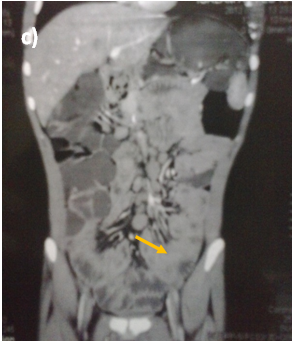

Abdominal ultrasound showed uniform circumferential mural thickening of the small bowel loops, so we proceeded to C.T Enterography. As shown in Figure 1, there is diffuse uniform thickening of the small bowel loops mainly involving the ileum with no focal thickening or masses. Then upper endoscopy and colonoscopy were performed to the patient and they showed multiple tiny rounded nodules at the terminal ileum that were biopsied and revealed non-specific inflammation free of granuloma or malignancy. Then we proceeded to double balloon enteroscopy which was done by an over tube double balloon Fuji series endoscopy, which proceeded to about 200cm from the duodenal bulb. Double balloon endoscopy as shown in Figure 2, showed numerous visible mucosal nodules measuring few millimeters in diameter involving the whole part of the small intestine examined which were biopsied. Histopathology revealed chronic inflammatory enteritis with foci of lymphoid aggregates with no atypia or malignancy (Table 1).

Figure 1 C.T. Enterography of the patient that showed diffuse uniform thickening of the small bowel loops mainly involving the ileum with no focal thickening or masses.

Figure 2 Diffuse small nodules scattered through the whole small intestine by double ballonenteroscopy.

Some reports had described DNLH in adult patients without immunodeficiency and it was thought to be associated with chronic GIT infections such as Giardiasis or Helicobacter pylori infection.4,8,10 Nodular lymphoid hyperplasia generally presents as an asymptomatic disease, but it may cause gastrointestinal symptoms like abdominal pain, chronic diarrhea, malabsorbtion syndrome, bleeding or very rarely intestinal obstruction.5 One of the most important issues likely to be raised is the differential diagnosis of this condition. Due to its characteristic appearance during endoscopy which appears as innumerable small nodules involving mainly the small intestine as shown in Figure 2 limits the differential diagnosis. Familial adenomatous polyposis (FAP) and intestinal lymphoma should be taken into consideration. GIT is considered the largest lymphoid system in the body, so intestinal diseases are not surprisingly associated with the immunodeficiency syndromes. Common variable immune deficiency is defined as deficiency of immunoglobulins mainly IgG associated with IgA, IgM or both.6 Selective IgA deficiency syndrome (SIgAD) is the most common primary immunoglobulin deficiency and is defined as the isolated deficiency of serum IgA (ie, in the setting of normal serum levels of IgG and IgM) in a patient whom other causes of hypogammaglobulinemia have been excluded.6–9 About 10 -15 % of the patients with SIgAD have symptoms of recurrent sinopulmonary infections, autoimmune disorders, gastrointestinal infections, anaphylactic transfusion reactions, Food allergies and respiratory allergies are prominent.6–9 There is an increased risk of malignancy in patients with DNLH and a coexisting hypogammaglobulinemia, especially the risk of lymphoma and gastric carcinoma. This is the typical scenario of our patient that was diagnosed after his presentation with intestinal lymphoma.11 DNLH with no complications usually does not require any special treatment. However, the patients should undergo the prophylactic examinations. For patients with chronic diarrhea repeated courses of antibiotics such as quinolones or metronidazole had been reported. Also eradication of Helicobacter pylori had significant reduction in the number and size of the nodules in some studies.4–12 This causes controversy when deciding the treatment options. Following up patients without any treatment may lead to malignant progression, while surgical treatment may result in justified radical resections.